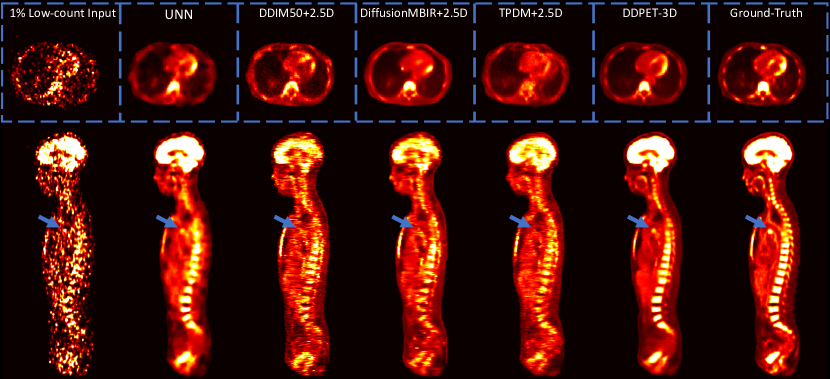

For comparison, we also extended the comparison diffusion models (DiffusionMBIR, TPDM, and DDIM), and re-trained them using neighboring slices as conditional information (denoted as DiffusionMBIR+2.5D, TPDM+2.5D, and DDIM+2.5D). Sample reconstruction results are presented in Fig. 11. Simply adding neighboring slices as conditional information does not necessarily lead to a better performance in other baseline models. Using the same testing patients in Table II, corresponding quantitative evaluations are presented in Table IV.